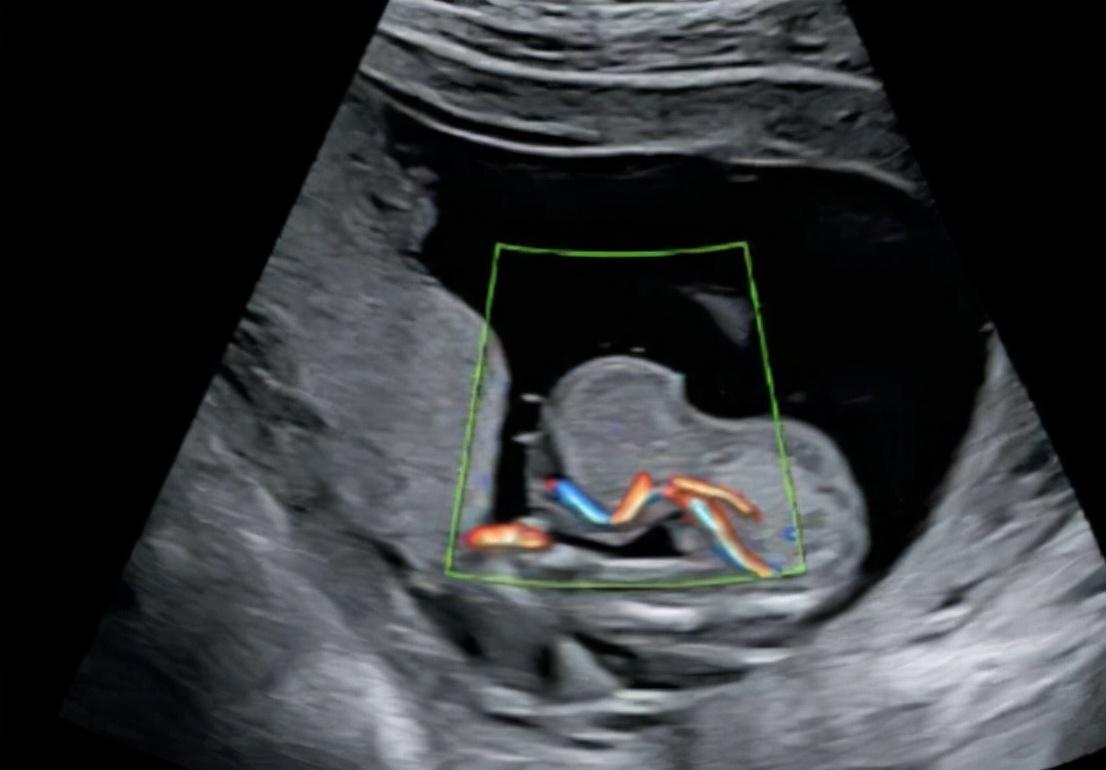

什么是腹腔妊娠呢?简而言之,就是胎儿长在了腹腔之中,在孕妇中,腹腔妊娠的出现概率,大约是三万分之一,和肝脏妊娠一样,都是极其罕见的。

虽然腹腔妊娠非常危险,但是,却也有成功案例,比方说在2007年12月,一名在腹腔中足月发育的胎儿,成功诞生于西安市的西京医院中,这也是我国首例腹腔妊娠成功诞生的婴儿,被取名为“小奇迹”。

不过,虽然母子平安,但是过程却是非常心惊动魄的,因为仅是在怀孕生产过程中,产妇就经历了多次转院,最终由宝鸡市转到了西安市,经过数小时的手术,才终于将孩子平安生了下来。